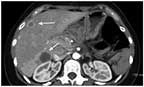

FIGURE 3

The Arrows Identify Liver Metastases, Which Were Pathologically Confirmed on CT-Guided Biopsy.

This patient’s tumor contained features associated with increased malignant potential, including large tumor size (13 cm) and a visible solid component.[5,8] Interestingly, although the patient developed radiographic evidence of liver metastases (Figure 3) within 4 weeks of repeat imaging, all 20 peripancreatic lymph nodes were negative for tumor, indicating pure hematogenous spread.